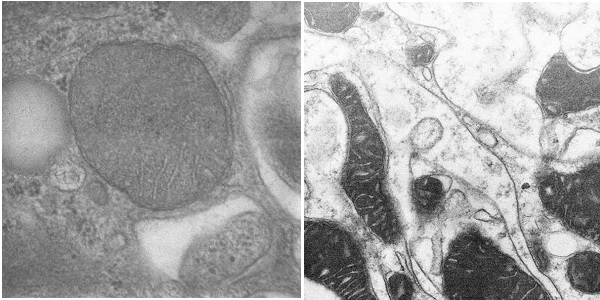

图4. 利用SmartView对病理组织切片样品进行成像(高倍STEM像)

项目从医院病理科电镜病理检测存在的仪器维护成本高、操作复杂、通量低、人力成本高等痛点出发,成功研制了针对病理组织切片样品的高通量扫描透射电子显微镜SmartView(图1),发明了载网托盘和新型的装载方式(图2),一次可以装载500个病理切片载网,实现了8K*8K的高速扫描透射成像能力,仪器成像分辨率优于1.1nm,可以进行病理组织切片样品高速和高质量成像(图3,图4),将有效推动生物医学病理电镜检测快速发展。